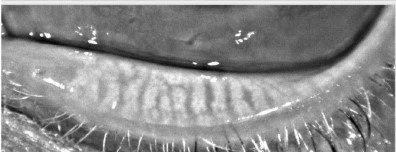

Meibomian Gland prior to Accutane